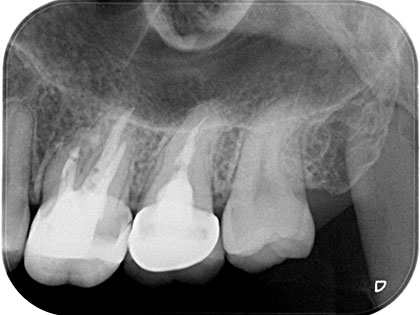

歯根端切除術

自分の歯を残す事が出来る治療の1つです。根の先の悪い部分を外科的に切除し治癒に導くための治療です。

• 根管治療を行ったが治らない、根管充填後に膿がたまり腫れてしまう

• 根管充填剤が根管外に漏れて感染し、根管治療では除去できず治せない

• 太くて長い土台が入っており外す際に歯根が破折するリスクがある場合